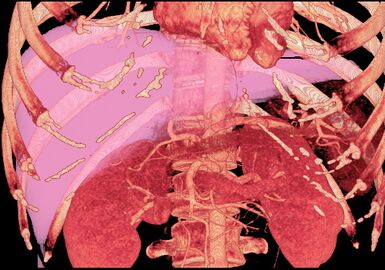

-

صورة مقطعية محوسبة بإسقاط الشدة القصوى (MIP) كما تبدو من الأمام تظهر الأوردة الكبدية الشاذة التي تمتد على السطح الأمامي للكبد.